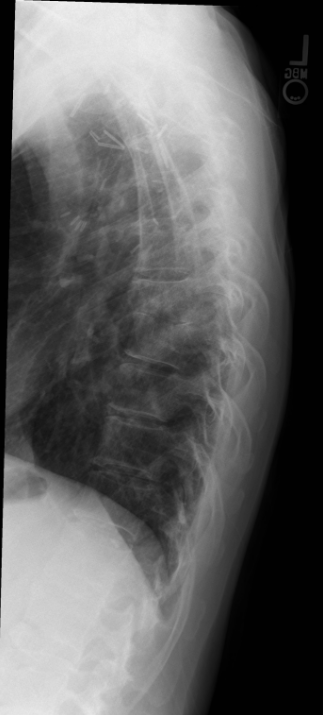

18

Q

This is spondylodiscitis.

Why is an infection in this area particularly dangerous?

19

What findings are on this radiograph?

What is the diagnosis?

A

• Anterior vertebral body destruction

• Endplate loss

• Disc destruction

Spondylodiscitis

acute suppurative infection